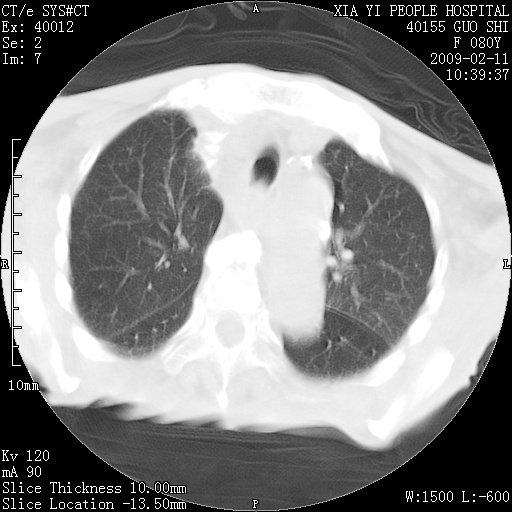

以下是引用随光逐影在2009-2-16 16:34:00的发言:[br]1)考虑右前纵隔皮样囊肿。2)双侧少量胸腔积液。

以下是引用zjzjr在2009-2-16 17:30:00的发言:[br]支持囊性畸胎瘤 双侧少量胸腔积液。